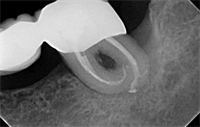

Dentaltown Learning Online..."Reciprocation - An Optimal New Paradigm in Root Canal Preparation" By Gianluca Plotino DDS, PhD; Nicola Maria Grande DDS, PhD; Prof Gianluca Gambarini, MD, DDS

Dentaltown Learning Online has now released an new course in Endodontics.......Reciprocation - An Optimal New Paradigm in Root Canal Preparation by Gianluca Plotino DDS, PhD; Nicola Maria Grande DDS, PhD; Prof Gianluca Gambarini, MD, DDS. This CE course can be found here.... ? Even if not...  Read More